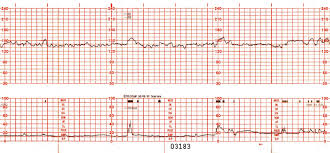

Observe el siguiente monitoreo fetal:

a) ¿A qué tipo de monitoreo fetal corresponde?

b) ¿Cuál es su interpretación?

a) NST

b) NST reactiva, Fcbasal: 140 lpm